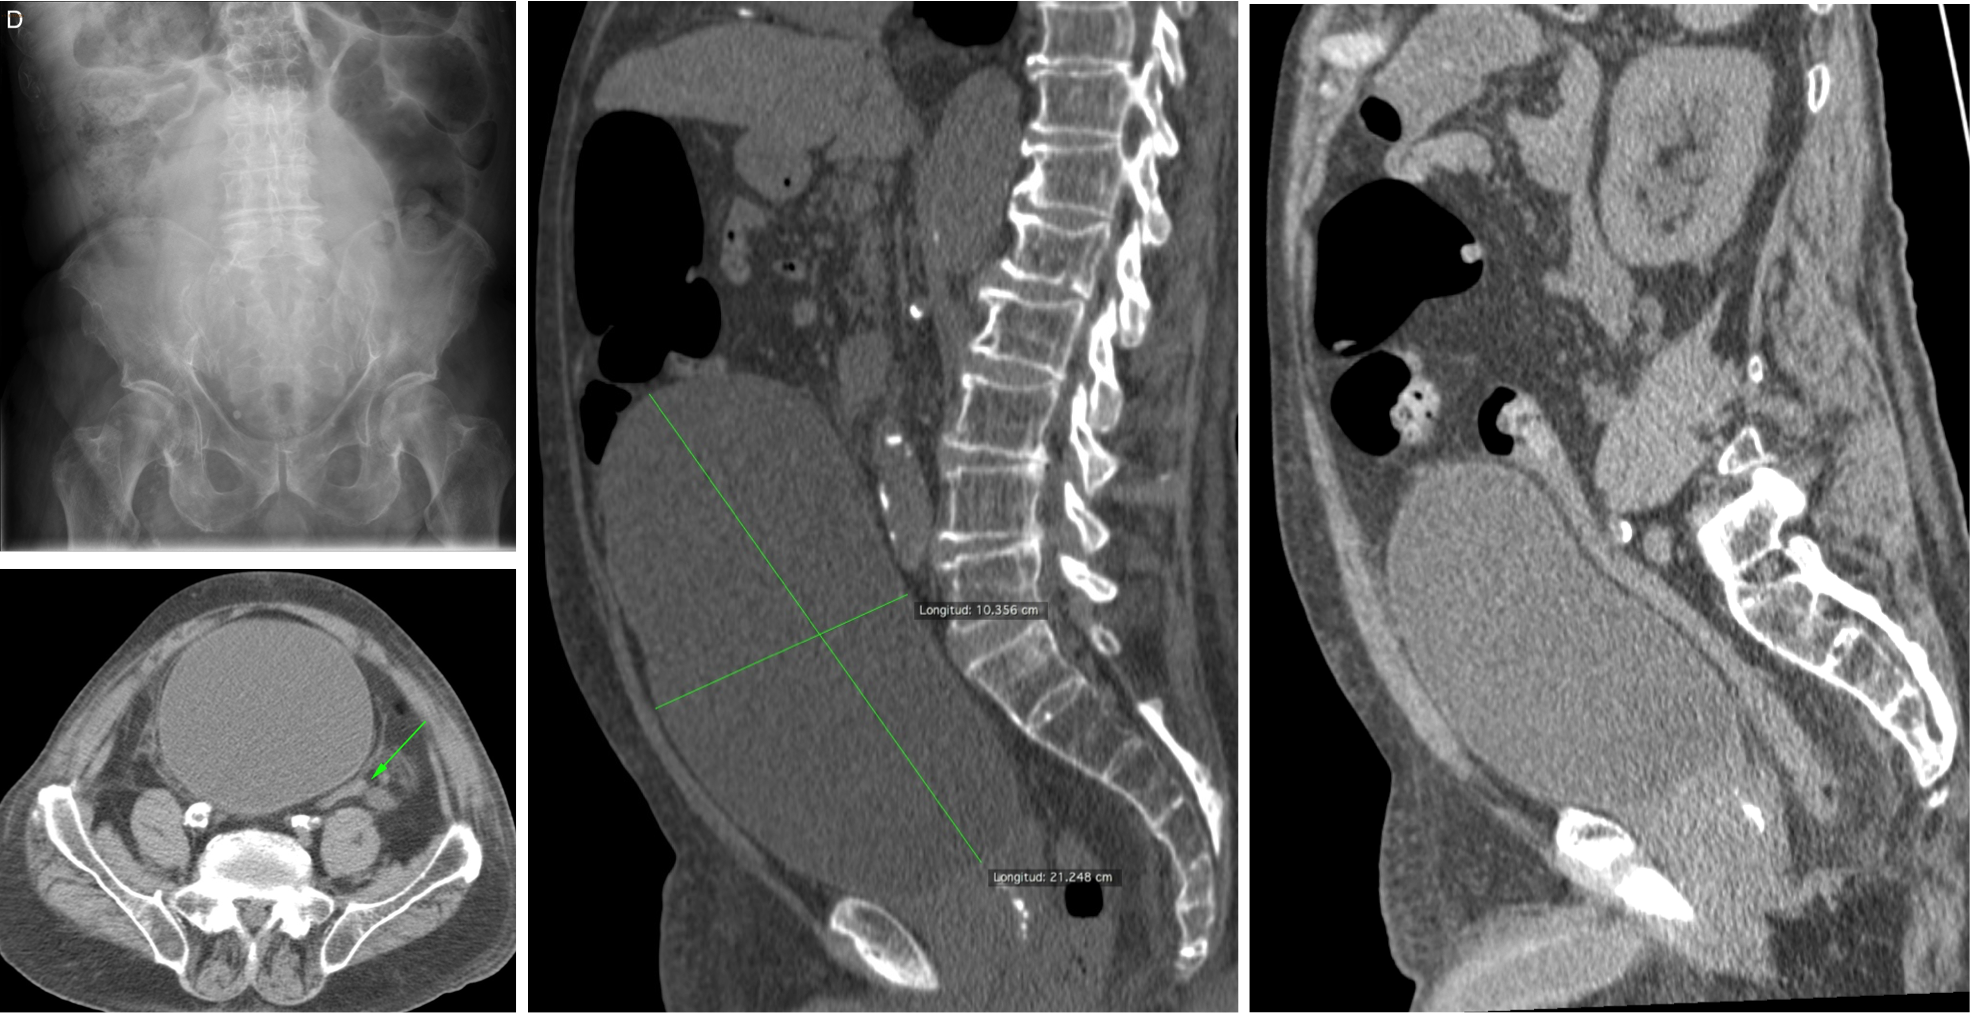

VÓVULOS.

Es una obstrucción en asa cerrada. Tambien nombraremos al vólvulo gástrico, que poduce una obstrucción alta.

En el vólvulo intestinal, los hallazgos en TC mostrarán una morfología “en grano de café”, dos tipos:

- De sigma: con vértice orientado hacia FII, morfología en “U invertida” y doble nivel hidroaéreo. No suele asociar dilatación de asas de delgado.

- De ciego: con vértice orientado hacia FID y único nivel hidroaéreo. Suele asociar dilatación de asas de delgado.